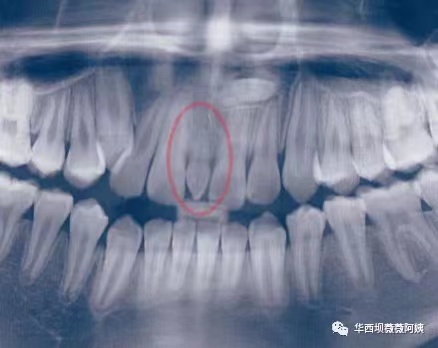

2.正中多生牙

刚才我们也讲过了,随着*牙虎**的萌出,会把门牙的缝隙关闭掉。但如果是门牙之间有多生牙,也就是多余的一颗或多颗牙胚占据了门牙之间的位置,那么即便*牙虎**萌出,也关闭不了这个缝隙。多生牙一般情况下都是建议拔除的。有些家长觉得既然多一颗,还不如留在那里,说不定以后还可以派上用场。

郑黎薇教授在此一定要告诉有这种想法的各位家长:多生牙不是存款,想用的时候再取。多余的牙胚占据了本该正常的牙齿该占据的位置,会产生很多后患,该拔就拔。不良资产一定要及时处置。

通常如果是因为正中多生牙产生的门牙之间缝隙增宽,这个宽度会显著大于生理情况下的中切牙间隙。